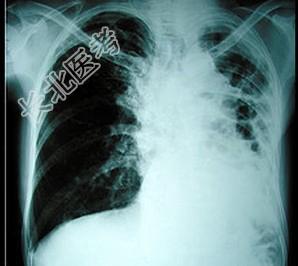

- 单项选择题患者因咳嗽、胸痛、乏力入院,体检时发现左肺呼吸音减弱, X线胸片如图所示,诊断为 ( )

A、支气管扩张

B、自发性气胸

C、肺结核

D、肺癌

E、以上均不正确